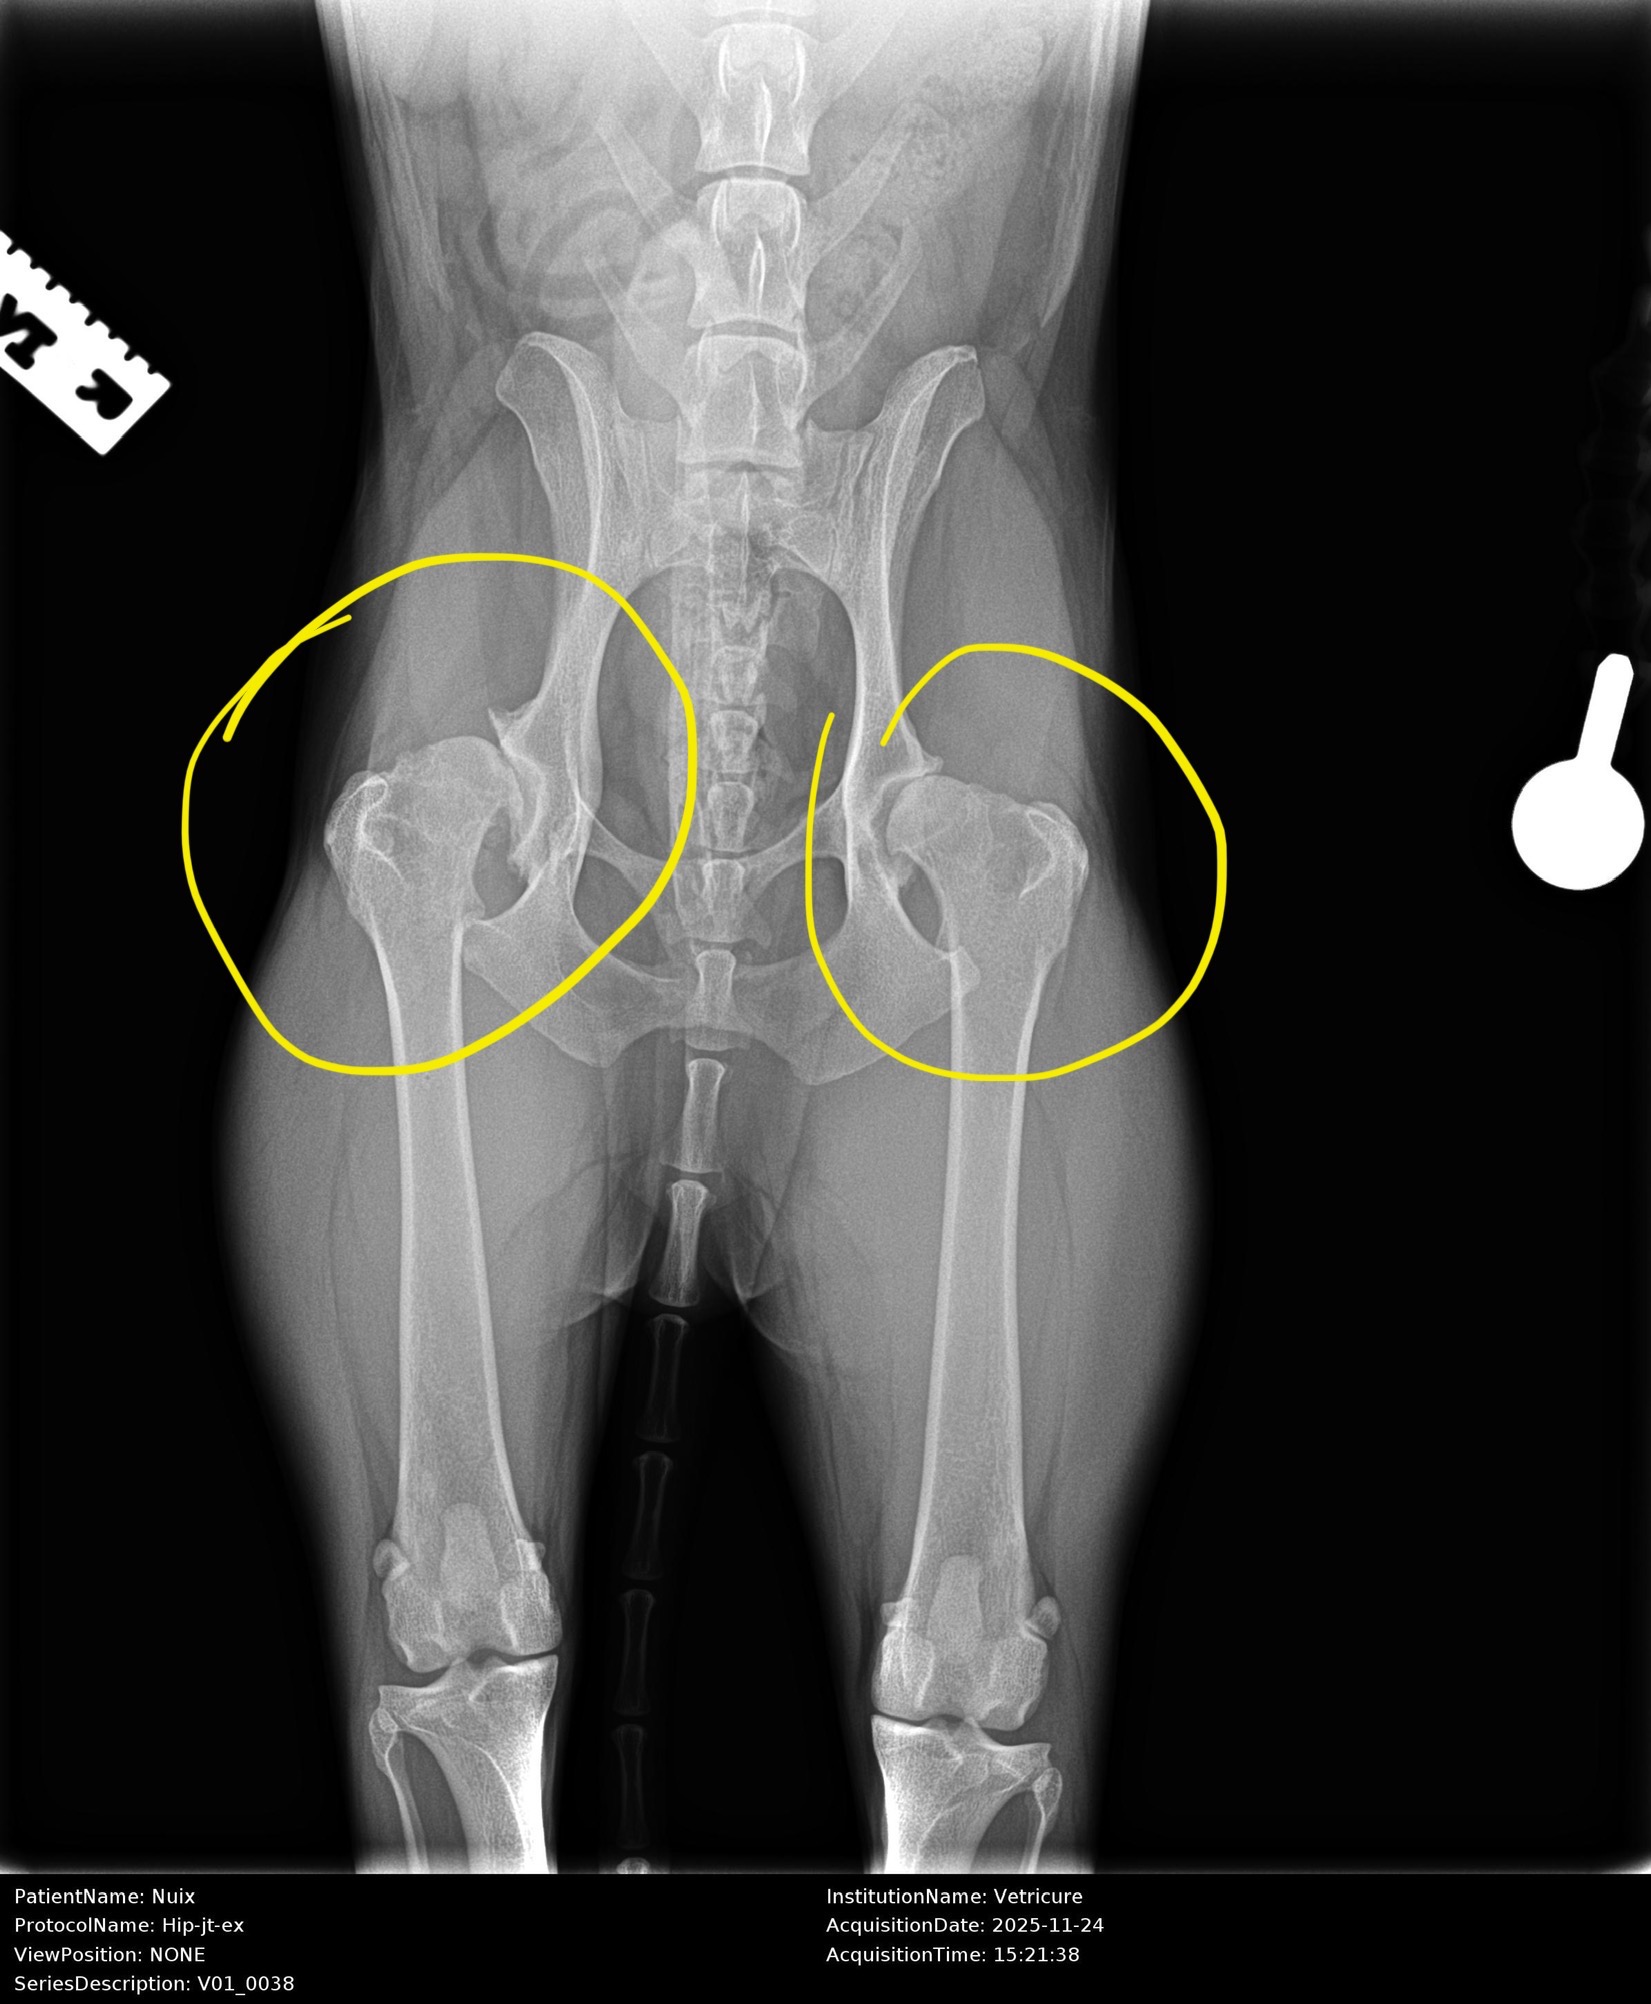

I’m only 5 years old, but my hips are very sick.

I have severe hip dysplasia and arthrosis, which means I can’t run, jump, or play like I used to.

Some days I don’t understand why my body won’t listen to me. I still want to chase sunsets and greet my family with my whole body wagging, but I can't anymore, because with one wrong movement my right hip can luxate, and the left one won't hold it together for long either.

The doctors say I urgently need two new hips so I can walk and play again. Each one costs €6,000, and my mom wants to save me, but she can’t afford it alone.